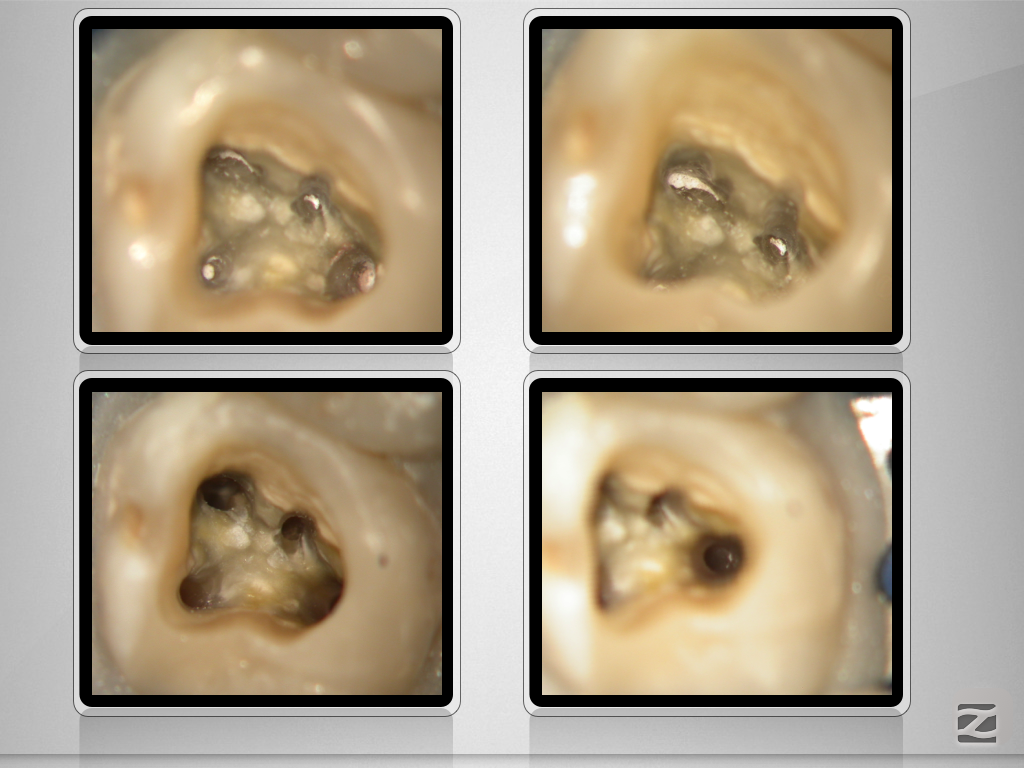

27d-neu-005

Vitales Gewebe – apikale Aufhellung